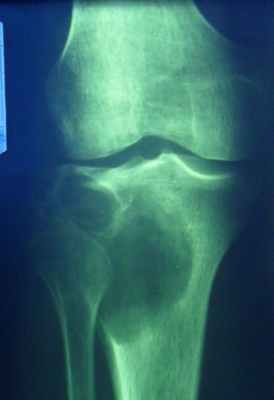

Гигантоклеточная опухоль

(остеобластокластома)

- состоит из клеток 2 типов- многоядерных гигантских и мелких одноядерных,

- поражаются люди в возрасте от 20 до 40 лет,

- локализация бедренная кость - дистальный конец, проксимальный конец б/берцовой кости, дистальный конец лучевой кости. Из плоских костей – тазовые кости и лопатка, очень редкая локализация в позвонках,

- одиночность и изолированность поражения,

- характерно расположение опухоли в эпиметафизраном отделе, который значительно вздут и деформирован, имеет вид крупнобугристого полушария, булавы,

- опухоль доходит до суставного хряща и обрывается,

- растет во всех направлениях, но главный рост происходит вдоль длинной оси кости в сторону с/3 диафиза кости,

- поперечник опухоли может увеличивать нормальный диаметр опухоли в 3-5 раз.

- ячеистый тип - опухоль состоит из отдельных камер, отделенных друг от друга полными и неполными перегородками (мыльные пузыри или неправильные соты),

- корковое вещество раздвигается, вздувается изнутри, истончается, надкостничных наслоений нет,

- при больших опухолях корковое вещество рассасывается и опухоль окружена со всех сторон тонкой скорлупой состоящая из стенок поверхностно расположенных ячеек.

- остеолитический тип – полное отсутствие ячеистого или трабекулярного рисунка, дефект кости вполне гомогенен,

- краевой блюдцеобразный дефект,

- корковый слой на пораженном месте рассасывается, а на границе с дефектом корка заострена, не подрыта и не имеет никаких периостальных наслоений,

- контуры дефекта резкие,

- патологические переломы в 12% случаев.